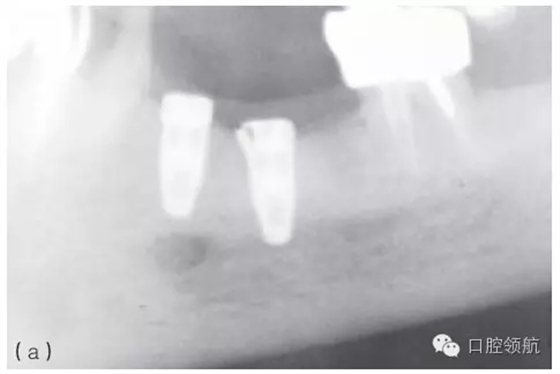

因種植體裝置界面的扭矩可能會使平臺連接出現(xiàn)潛在的變形,故應(yīng)注意使該扭矩最小化。Ⅳ類骨植入種植體時要優(yōu)先在骨上敲打擠壓而不是依靠種植體來擠壓骨洞。許多廠家會提醒不要超過手術(shù)操作時推薦的扭矩,以減小折斷的可能性(圖5.3a~c)。

圖5.3 (a)Ⅰ類骨中的種植體內(nèi)連接和界面破損的影像學(xué)表現(xiàn)。(b)取出種植體,發(fā)現(xiàn)沿著種植體平臺的損壞。(c)在重新放置的種植體上行聯(lián)冠修復(fù)完成2年后的影像學(xué)表現(xiàn)。